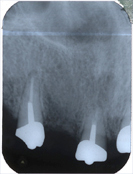

In den Abb. 2 und 3 sind auf zwei Kontrollröntgenbildern neun Jahre nach der Wurzelbehandlung (Endodontie) einwandfreie, entzündungsfreie Knochenverhältnisse im Oberkiefer sichtbar.